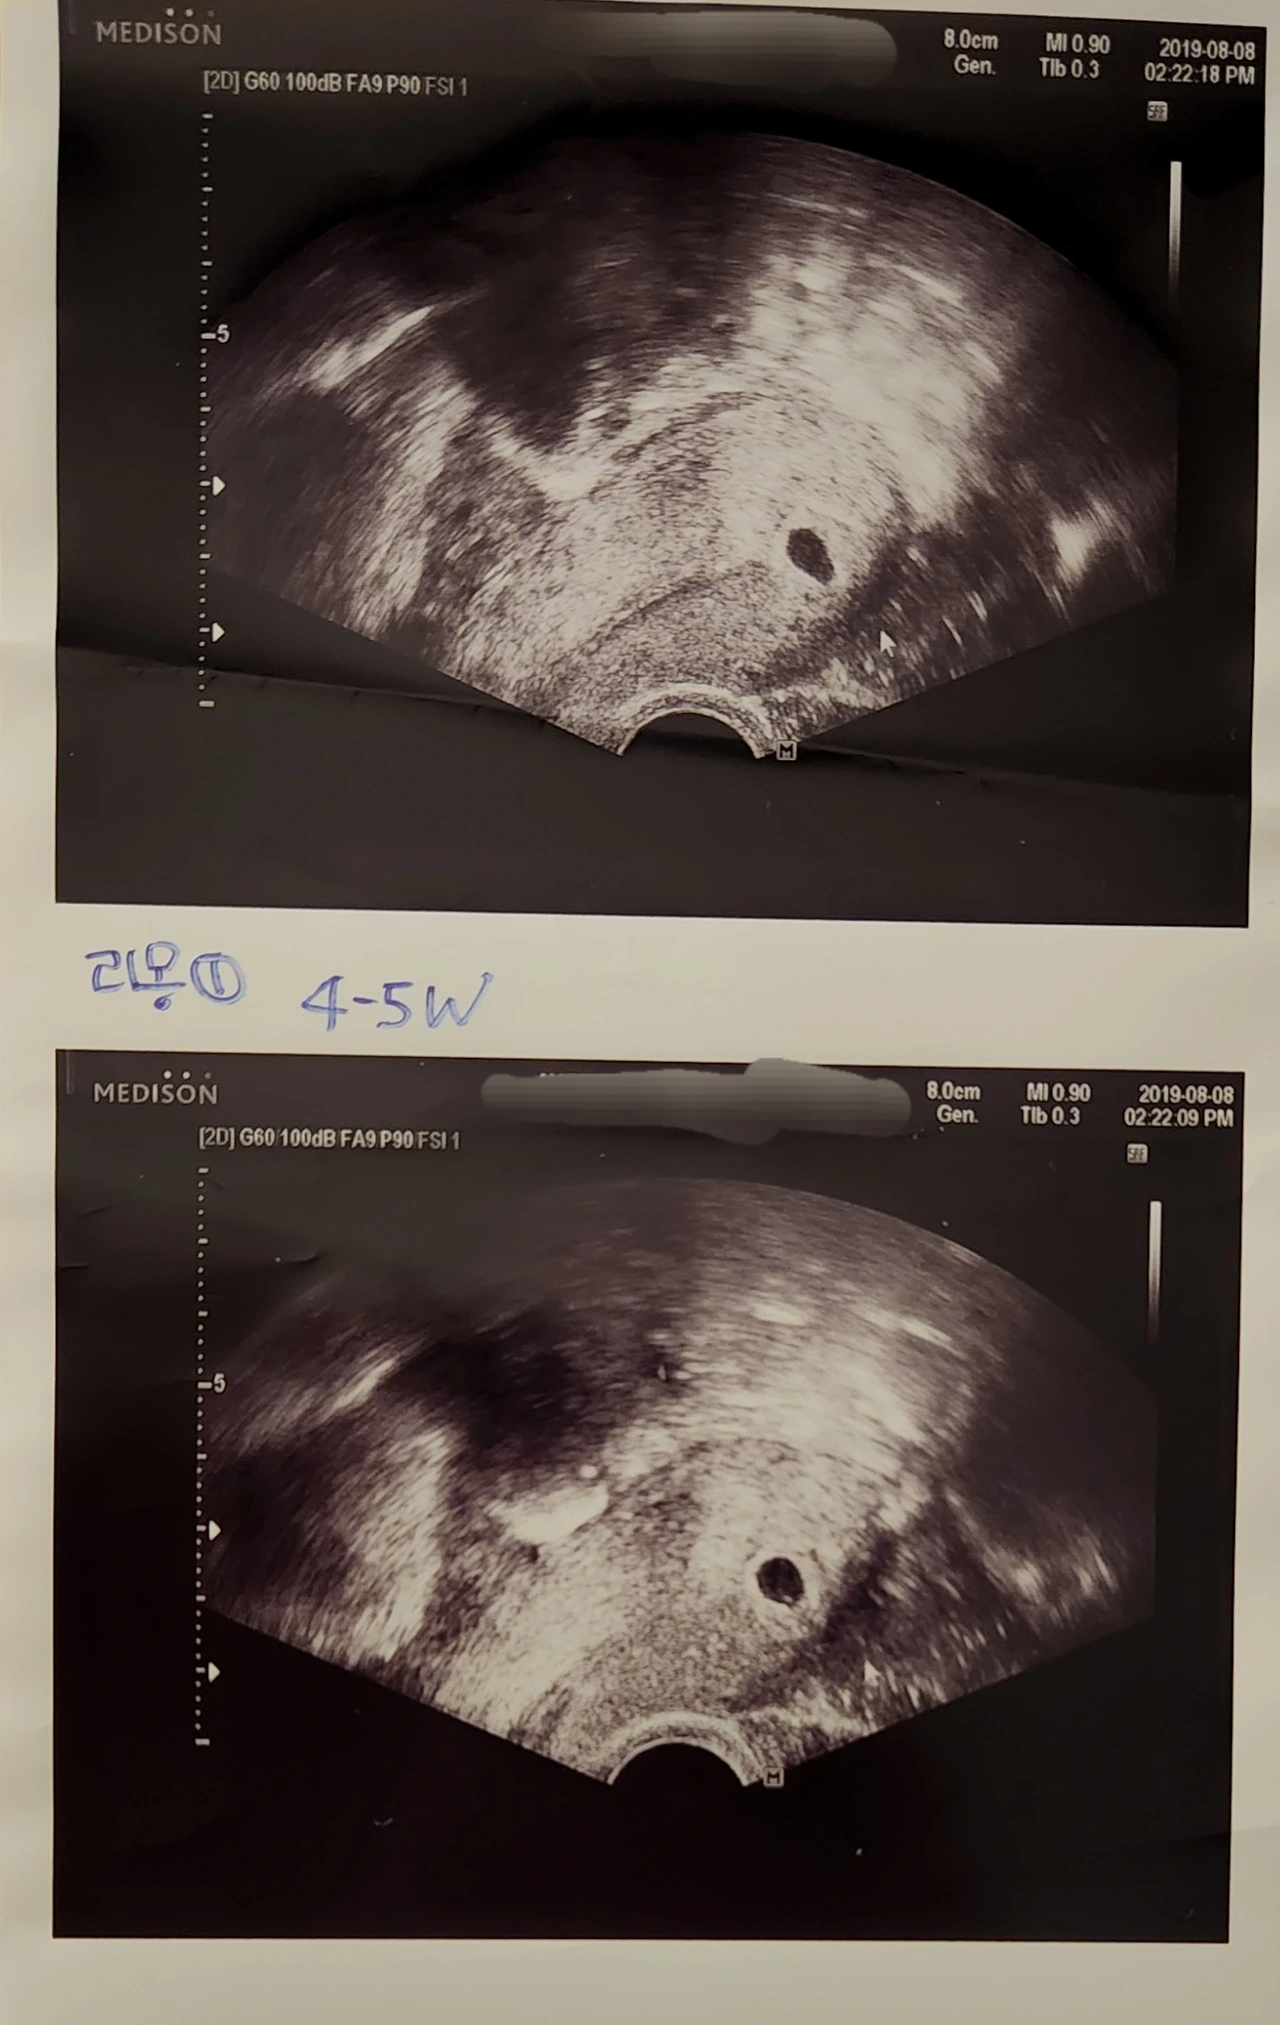

둘째이자 태어나기로는 첫째를 임신했을 때 특히 9주까지는 아기가 어떻게 될까 매번 산부인과 검진 시 "심장은 뛰나요?"를 나도 모르게 가장 먼저 물어봤더랬다.